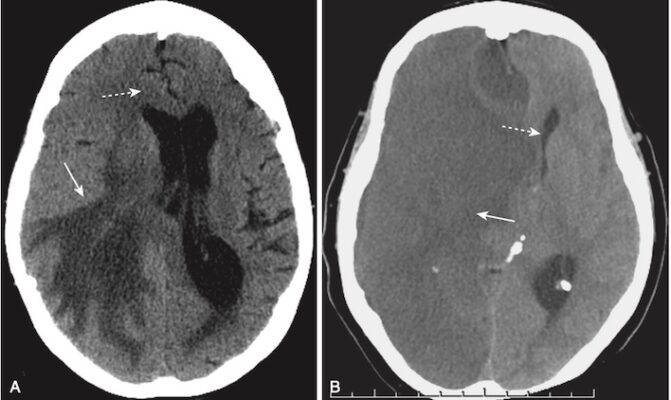

- Một trong hai cơ chế này có thể tạo ra dập não (contusion). Các đụng dập xuất huyết là những xuất huyết, kèm theo phù nề, thường thấy ở phần dưới thùy trán và phần trước thùy thái dương trên hoặc gần bề mặt của não (Hình 10).

- Nhận biết xuất huyết trong não do chấn thương trên CT:

- Đụng dập xuất huyết não có thể xuất hiện dưới dạng nhiều vùng nhỏ, được phân cách rõ ràng với đậm độ cao trong nhu mô não (xem Hình 10, A).

- Chúng có thể được bao quanh bởi một vành giảm tín hiệu (hypodense) do phù nề (xem Hình 10, B).

- Hiệu ứng choán chỗ thường gặp. Hiệu ứng choán chỗ có thể ép các não thất và đẩy lệch não thất thứ 3 và vách ngăn sang bên đối diện. Sự dịch chuyển như vậy có thể gây ra tổn thương não hoặc mạch máu nghiêm trọng.

- Những di lệch này được gọi là thoát vị (herniation). Những bệnh nhân có hiệu ứng choán chỗ đủ lớn có nguy cơ bị thoát vị não qua lều hoặc dưới liềm và tử vong (xem Hình 10, B). Các dạng thoát vị não được mô tả trong Bảng 5.